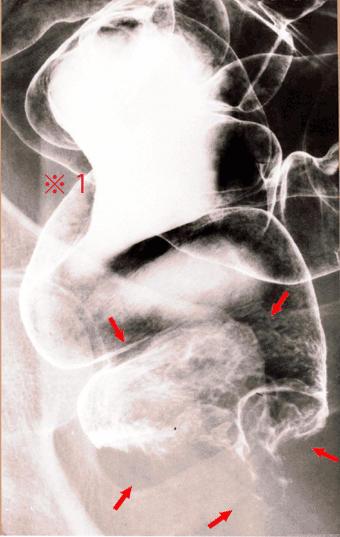

直腸の悪性黒色腫の注腸X線像。 直腸下部〜肛門部に、多結節性の結節状隆起が存在します(矢印部)。一方、直腸上部にはリンパ節転移による圧排・圧迫所見が認められます(※印)。二重造影像でみると、腫瘍は大きな結節状の腫瘤を形成し、また肛門側では、表面は凹凸不整を示しています。

疾患(病理主体)の分類悪性黒色腫/

部位(臓器別)大腸/直腸

検査方法X-P

病変の最大径(ミリ)40以上

腫瘍の深達度mp